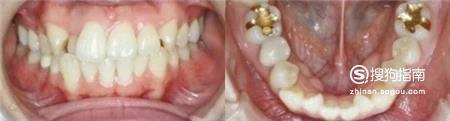

矫正之前,可以看出,虎牙很明显,参差不齐,上下牙齿排列也不整齐。

下排拔牙后的空间正在慢慢闭合,虎牙的形成是由于在有限的口腔内,牙齿萌出时周边空间不足导致牙齿里进外出,现在我们可以看出正在把突出的牙齿往回拉。

第五个月和第八个月对比图,我们可以大致看出一些变化。

矫正开始后每个月都要去一次牙科进行月诊,3个月的功夫虎牙就变得整齐了。

其他牙齿也开始移动,牙齿间的空隙慢慢闭合,脸部的轮廓已经在慢慢变化了。

最后效果还是很理想的,变化真的很大呢!